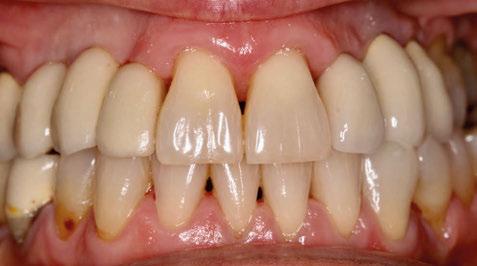

-Registros fotográficos intra y extraorales (Figura 1 a-c).

Figura 1a. Foto intraoral frontal inicial.

Figura 1b. Foto intraoral lateral izquierda inicial.

Figura 1c. Foto intraoral lateral derecha inicial.

25, 26, 28, 37, 38, 47 y 48. Presentaba corona desajustada en 13 con extensión en 12, implantes en 35-36, 45-46, con coronas ferulizadas en 35-36, 45-46, y dientes anteriores superiores con enfermedad periodontal Grado IV.

2. Exploración de tejidos blandos

El paciente presentaba biotipo periodontal grueso, con márgenes asimétricos, con recesiones gingivales a nivel de 11 y 13 y pérdida de tejidos blandos interproximales.